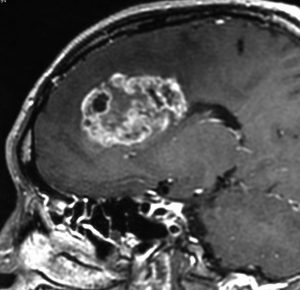

40代の患者さんです。夜間睡眠中の全般発作(症候性てんかん)で発症しました。フレア画像で左上前頭回に滲むような高信号領域(白い部分)がみられます。右側はガドリニウム増強MRIですが,全く増強されません。グレード2か3の星細胞腫あるいは乏突起膠腫を疑います。白く滲むような領域はよく見るとかなり広範囲に広がっています。

画像上では全摘出 gross total removalできて,病理診断は,退形成性乏突起星細胞腫 anaplastic oligoastrocytomaでした。IDH変異あり,1p/19q欠失なしです。現在の診断なら,退形成性星細胞腫 グレード3です。

手術後に54グレイの広範囲な局所放射線治療とテモゾロマイド化学療法を行いました。左の画像は放射線治療計画の時の線量分布図です。

5年後にいきなり激しい再発を生じました。再発部位は,放射線照射野外 out-of-fieldの前頭部帯状回でした。手術前に急速に増大して,画像所見も初回と全く違いました。摘出後の病理は,IDH1/2 wild type, 1p/19q intact, ATRX negative, MGMT met negative, MIB-1 40%という典型的な膠芽腫の所見でした。

この例とは異なって,退形成性星細胞腫の再発時には,IDH mutantのままの方が多いです。もしかすると先行した放射線誘発膠芽腫かもしれません。